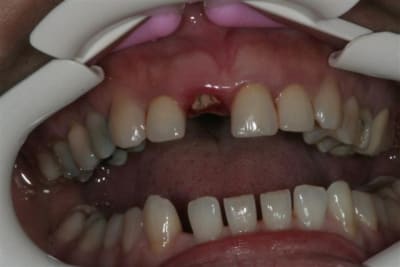

entre temps il y a de l'odf pr réaligner les incisives du bas(diastèmes se modifient d'après la patiente), à la demande de la patiente et parceque la fracture de 11 au bout de tant d'années me questionne...

la CCM est en prov de luxe

(ça tombait bien,la teinte est moyenne,bien qu'elle passe mieux en bouche que sur la photo:le flash?)

la patiente part en vacances

je la referai en septembre

avec ou sans chir?...

il y a eu remodelage naturel(comme quoi entre la theorie et la clinique): peut on le considérer comme suffisant?

autre question:"les incisives du bas"

la patiente a entamé son traitement odf pr une demande esthetique(marre des diastème)

pr des raisons fonctionnelles aussi,cela ns paraissait une bonne idée

elle a une microdontie relative de ces insicives qui st maintenant redressées, alignées avec des diastèmes equidistants

et maintenant....

que feriez vous?

on comprend mieux la microdontie relative

les diastemes te genent? tu as peur de la recidive apres l'ortho?